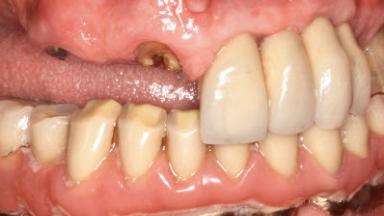

Retreatment of a Patient with Multiple Biological and Technical Complications and Failures

A 66-year-old patient presented because of retention loss of the tooth-supported FDP in the right maxilla (x-13-x-11). The mandibular full-arch implant-supported reconstruction (x-i34-i33-x-x-x-x-i43-i44-x) had suffered extreme wear. His medical history revealed high blood pressure, controlled with anti-hypertensive medication. The patient was a light smoker (2 to 3 cigarettes per day). The existing reconstructions had been performed alio loco about five years previously. That treatment had taken an extensive amount of time, and as early as during the fabrication of the reconstructions, multiple complications had occurred with the provisionals.